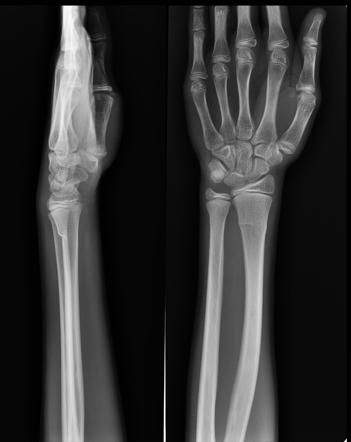

Torus Fracture - यात हाड तुटत नाही पण हाडाचा आकार बदलल्याने वेदना होतात.

Transverse Fracture - हाडाचा सरळ सरळ मध्यभागातून तुकडा पडणे.